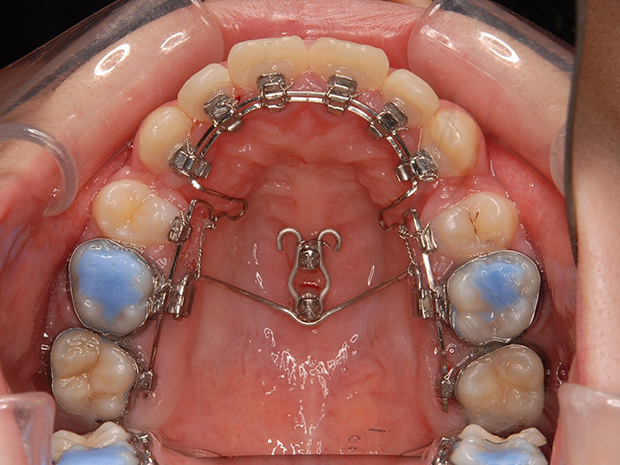

【ハーフリンガル】叢生 抜歯 上顎舌側マルチブラケット装置

| 主訴 |

ガタガタ |

||

|---|---|---|---|

| 診断名 |

右側Angle II級叢生 |

||

| 年齢 | 19歳 | 性別 | 女性 |

| 治療に用 いた装置 |

ハーフリンガル装置 (セミカスタム) | 抜歯部位 | 上顎両側第一小臼歯 下顎両側第二小臼歯 |

| 治療期間 ・回数 |

2年・24回 | 治療費 概算 |

約85万円 (調整料を含む) |

| 治療内容 詳細 |

歯科衛生科に入学し、自分の歯ならびが気になり始めたとのこと。上の歯列のみ舌側矯正(裏側矯正)、下は表側の、ハーフリンガルで治療を行いました。 |

||

| リスク・ 副作用 |

装置による違和感。疼痛、歯根吸収など |

||